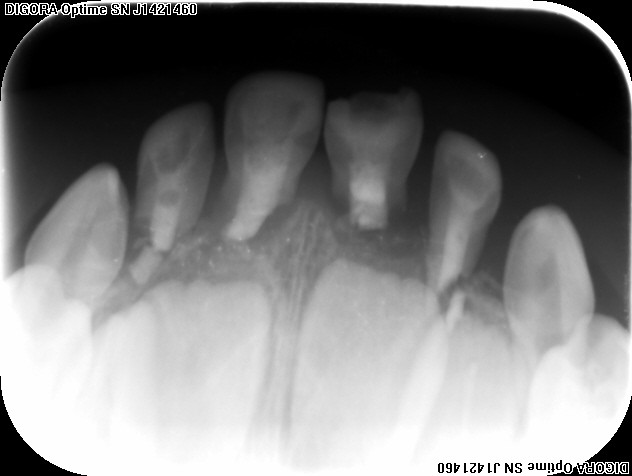

4 верхних резца восстанавливали в 1,5 года. Сейчас 3,5. Две с половиной недели назад - бежал, упал, сильно ударился в десну, кровь, слезы и центральных два резца пошатываются. Снимок показывает, что все 4 сломаны и корни рассосались? Правильно? Итак, учитывая все вышеописанное - мы просто ждем, когда они сами выпадут? Может ли развиться, например, воспаления, из-за того, что они сломаны? Что теперь будет происходить с зубами (про себя уже молчу)))?